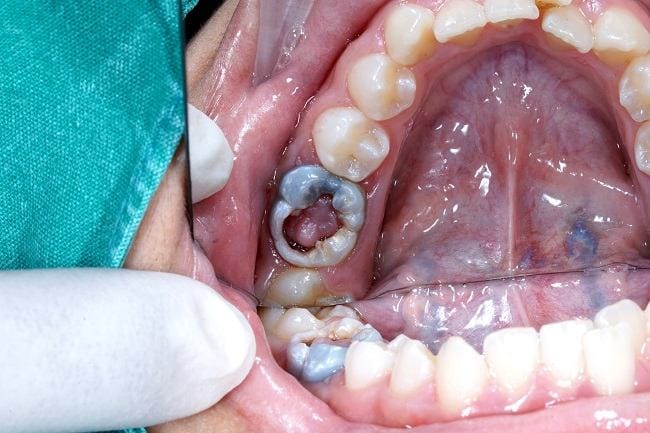

- Benjolan lunak berwarna merah muda, merah, atau putih dari gigi yang berlubang

- Perdarahan dan luka terbuka dari benjolan lunak tersebut

- Polip yang cenderung membesar sampai memenuhi lubang di gigi